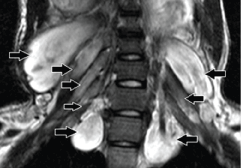

Figure 14: A 16-year-old male with neurofibromatosis type 1. Coronal fatsuppressed T2-weighted MR image shows diffuse, fusiform, longitudinally oriented hyperintense lesions involving all the pre and postganglionic cervical nerve roots (arrows) of BP bilaterally without any definite capsule.